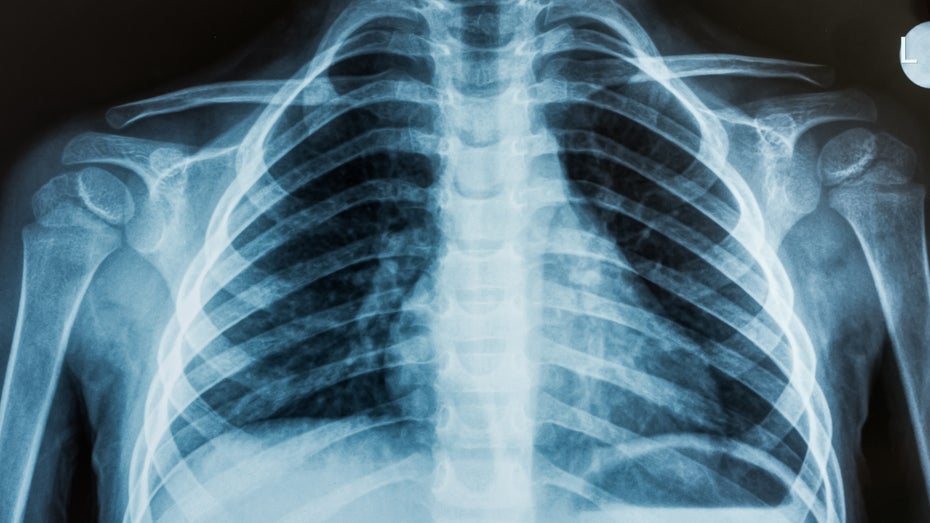

Das Röntgenbild eines Brustkorbs. (Foto: OZMedia / Shutterstock)

Das litauische Unternehmen Oxipit hat ein Tool entwickelt, das mithilfe von künstlicher Intelligenz in der Lage ist, die Röntgenaufnahmen eines menschlichen Brustkorbs ohne Aufsicht eines Radiologen zu lesen. In der vergangenen Woche erhielt das Tool die behördliche Genehmigung für seinen Einsatz in der Europäischen Union.

Das Tool namens ChestLink scannt Röntgenaufnahmen des Brustkorbs und versendet automatisch Patientenberichte über diejenigen, bei denen keine Anomalien erkennbar sind. Alle Bilder, die das Tool als potenziell problematisch kennzeichnet, werden zur Überprüfung an einen Radiologen gesendet. Da die meisten Röntgenaufnahmen in der Grundversorgung keinerlei Probleme aufdecken, könnte die Automatisierung des Prozesses für diese Scans die Arbeitsbelastung von Radiologen verringern.